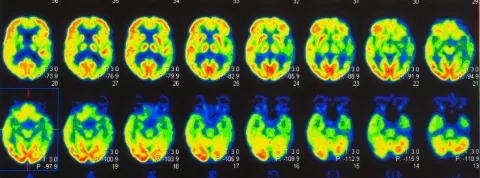

La tesis, titulada “The dynamic nature of conceptual representations in the human brain: Insights from aging and decoded neurofeedback”, fue desarrollada en el Basque Center on Cognition, Brain and Language (BCBL) en colaboración con la Universidad del País Vasco, y analiza cómo el cerebro representa los conceptos a lo largo de la vida y cómo esas representaciones pueden ser modificadas mediante estimulación cerebral indirecta.

A través del uso de decoded neurofeedback basado en resonancia magnética funcional (fMRI-DecNef), Margolles explora si es posible alterar, de forma implícita y no consciente, los patrones neuronales asociados a significados complejos. Lejos de entender el envejecimiento como una pérdida, su estudio lo revela como una reorganización funcional del sistema conceptual.

Tradicionalmente el envejecimiento se ha asociado con un proceso de deterioro global de las funciones cognitivas. Sin embargo, en el envejecimiento sano, el conocimiento semántico tiende a preservarse. En el marco de esta tesis y de nuestra publicación en Neuropsychologia, mediante una amplia variedad de análisis computacionales, hemos observado que la arquitectura cerebral que sostiene las representaciones de los conceptos va cambiando con el paso del tiempo. Así, lejos de implicar una pérdida de contenido, el envejecimiento parece dar lugar a una reorganización en la manera en que los conceptos se codifican y se activan en el cerebro. En concreto, los límites entre categorías semánticas amplias parecen volverse más difusos con la edad. No obstante, dentro de cada categoría, los patrones de activación cerebral de los conceptos presentan una mayor diferenciación entre sí, lo que sugiere una especialización más precisa a nivel local. Esta reorganización sugiere que, con el envejecimiento, el sistema semántico experimenta una adaptación o compensación funcional destinada a preservar el rendimiento.

Es una técnica que usa resonancia magnética funcional en tiempo real y algoritmos de IA para reforzar patrones neuronales sin que la persona sepa qué está entrenando. Permite modificar representaciones mentales complejas de forma implícita. La aplicación de esta técnica en mi tesis la presentaré en las IV Jornadas de la Cátedra VIUNED. ¡Allí os espero!